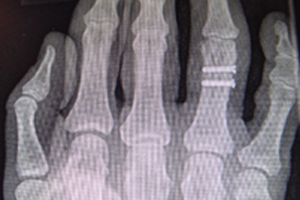

Wegen eines verbliebenen Rotationsfehlers des rechten Ringfingers wurde der Klägerin anderenorts eine Korrekturoperation empfohlen (s. Abb.3

3. In den postoperativen Röntgenkontrollen sei die radiale Abweichung des rechten Ringfingers erkennbar, die einen Drehfehler ohne gesicherten Hinweis nicht ganz ausschließen ließe.

5. Die Fraktur sei in Fehlstellung ausgeheilt. Aus den vorliegenden Dokumenten würde nichthervorgehen, welche weiteren Therapieoptionen diesbezüglich in Anspruch genommen seien.

Es bestand am 22.05.2020 eine tragfähige Indikation für eine offene Reposition und osteosynthetische Versorgung der dislozierten Mehrfragmentfraktur am rechten Ringfingergrundglied. Das ärztliche Vorgehen war fehlerhaft, weil die Fraktur nicht achsengerecht versorgt wurde, ein Rotationsfehler verblieb und eine zeitnahe Korrektur nicht eingeleitet wurde. Die Ärzte der beklagten Klinik räumten in ihrer Stellungnahme ein, dass eine Fehlstellung des rechten Ringfingers vorgelegen habe. Die Drehfehlstellung des rechten Ringfingers sollte sich durch Krankengymnastik und Ergotherapie korrigieren. Eine zeitnahe Korrekturosteotomie war jedoch indiziert. Entscheidend zum Nachweis einer achsengerechten Stellung und zum Ausschluss eines verbliebenen Rotationsfehlers sind die klinischen intra- und postoperativen Stellungskontrollen der Finger beim aktiven und passiven Faustschluss und der Lauf der Finger (Abb.4)